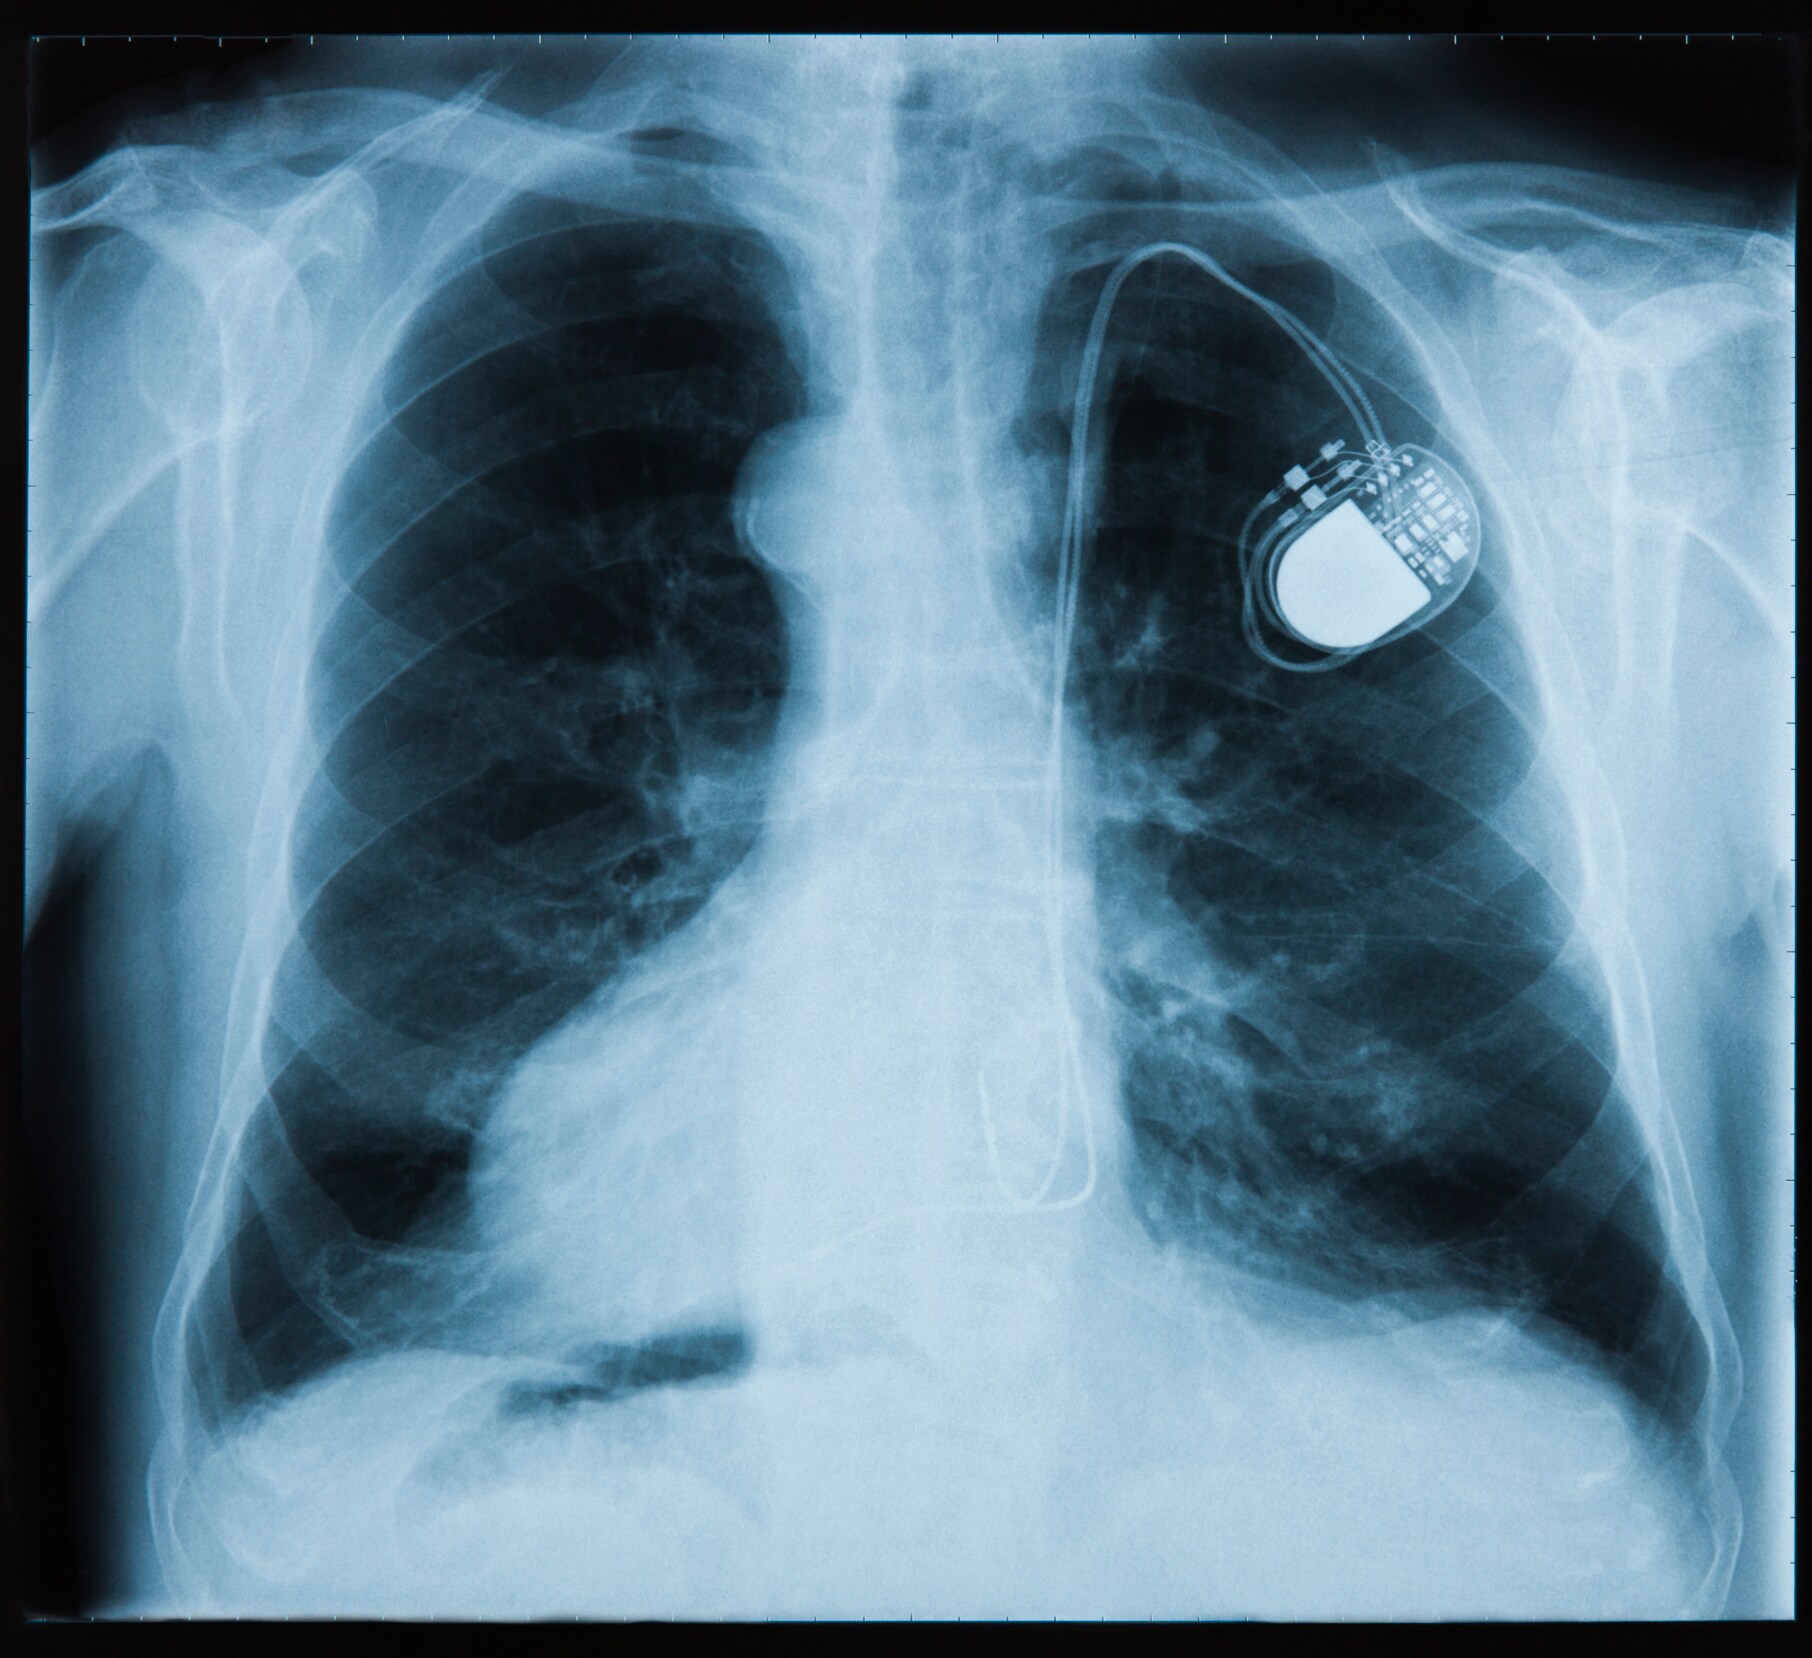

Most pacemakers contain at least two platinum-iridium electrodes.

Platinum is inert, rarely causes allergic reactions, has good electrical conductivity, and can be fabricated into tiny components, all qualities that make it an ideal material for pacemakers, stents, implantable defibrillators, and catheters. Most pacemakers contain at least two platinum-iridium electrodes. Platinum marker bands and guide wires are commonly used to place stents, and now even the stents themselves may be made with platinum alloys. Platinum marker bands are also placed on catheters and guide wires to help surgeons with device placement. Platinum-iridium electrodes are used in neuromodulators such as aural and retinal implants as well as devices used to treat Parkinson’s disease and chronic pain.